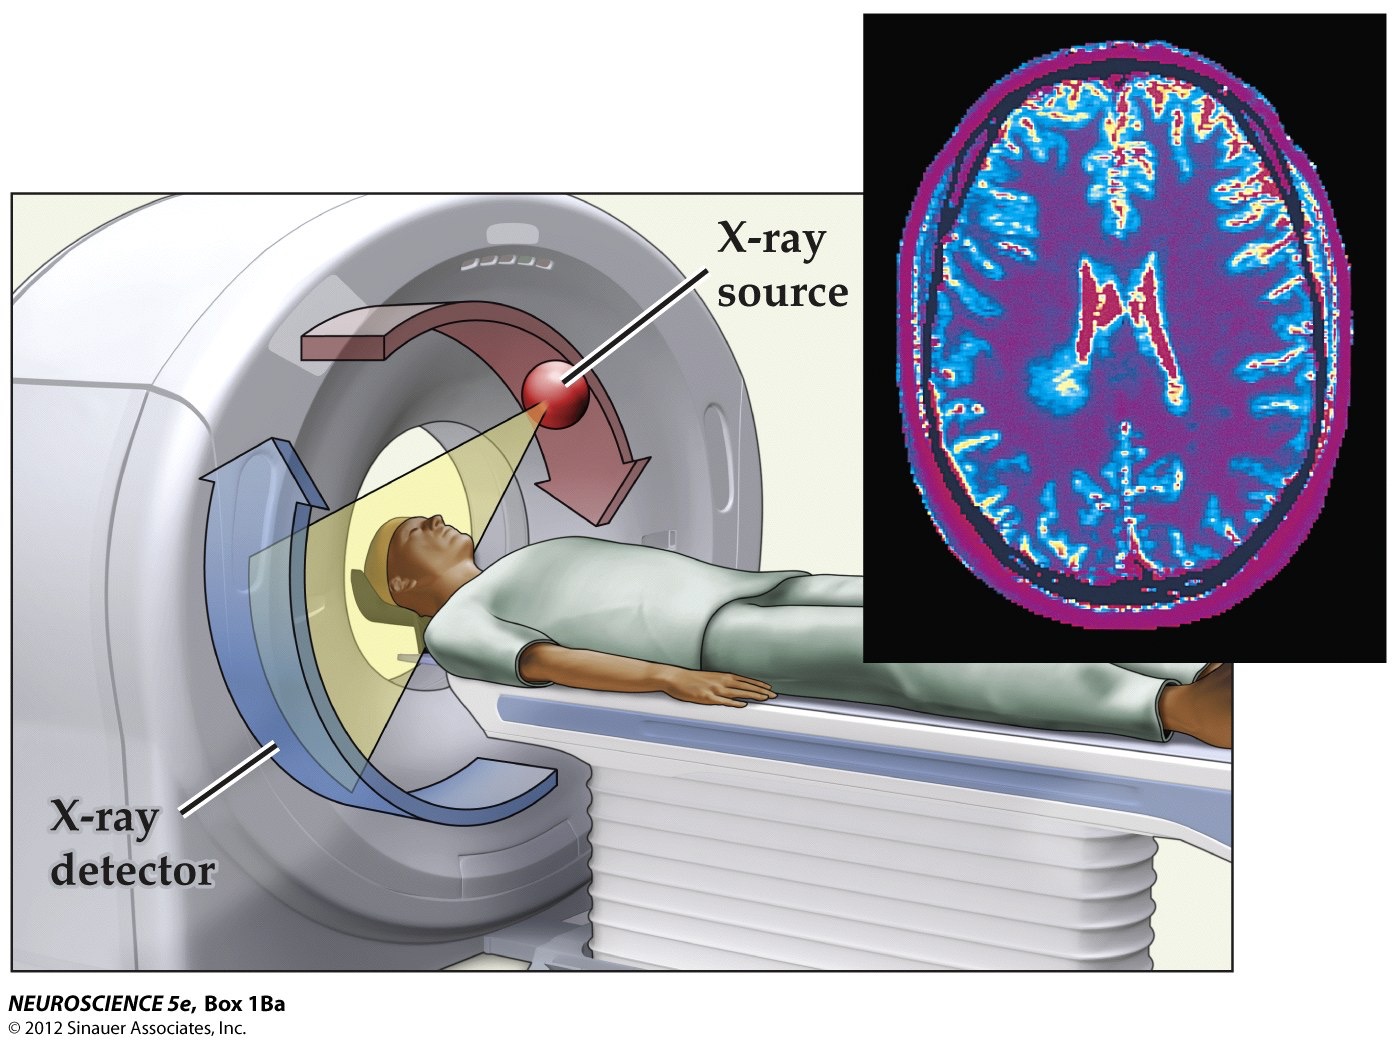

Brain imaging techniques

- Computerized tomography (CT) scan– uses X-rays in 3-dimensions to generate a brain image

- Can be digitally sectioned to show internal areas of the brain

- Can distinguish between grey matter and white matter, see the ventricles, has resolution of several millimeters

Note: